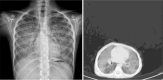

Chest x.ray and CT-Scan of patients with PAP.